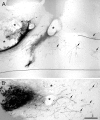

Fig. 5.

Two examples of BDA-labeled corticospinal fibers at the lesion site in animals treated with rIN-1. Sagittal 50 μm vibratome sections. A, Overview of a typical lesion area in a rIN-1 Fab-treated animal 2 weeks after injury. The labeled corticospinal tract, which runs at the medioventral aspect of the dorsal funiculus in the rat, approaches the lesion from rostral (left) and is interrupted at the lesion. Cellular infiltrates and cavities are present (asterisks).Arrows indicate regenerated fibers that have circumvented the lesion area and are growing in a typical curved and irregular pattern away from the lesion in the caudal direction.B, A close-up in a different rIN-1 animal shows that regenerating fibers growing around and through the lesion are very tortuous and curved. Scale bar (shown in B):A, 100 μm; B, 25 μm.